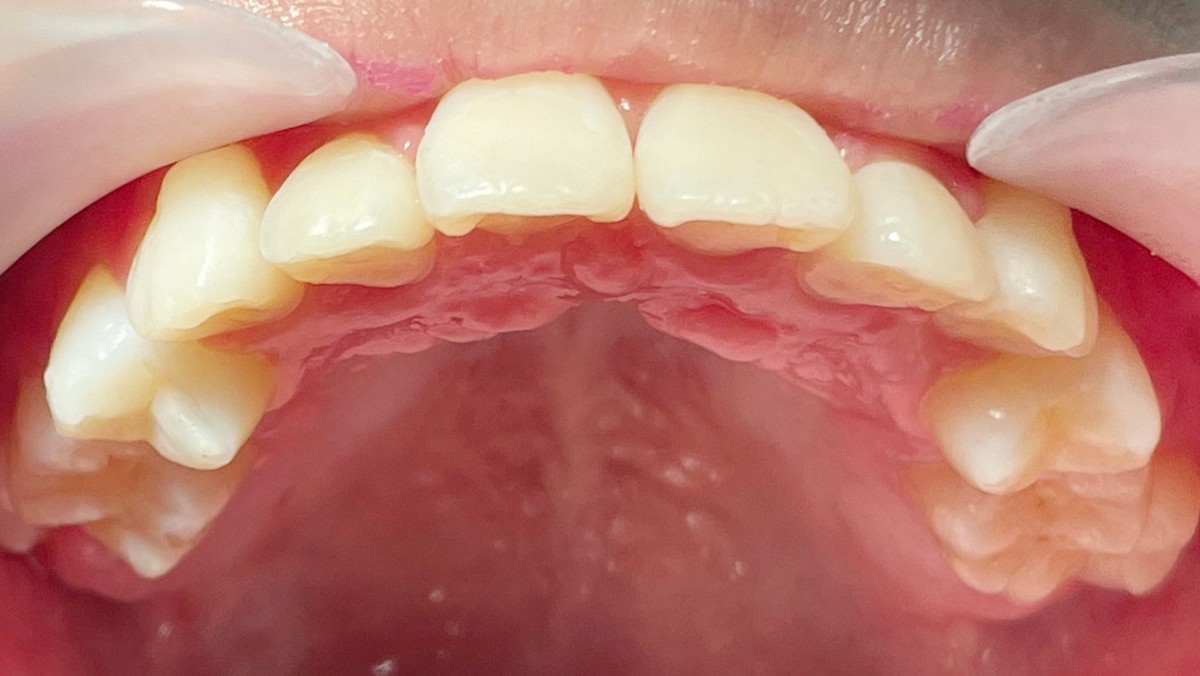

正在換牙期的小茹因齒列先天發育異常,從小就咬合不良,雖然能正常飲食,也不影響說話,但是一口亂牙令她相當困擾,因此在11歲時被媽媽帶來台北慈濟醫院齒顎矯正科評估。全口X光中看到小茹的牙齒不但亂,還有先天缺牙與阻生齒。陳宜宏醫師建議早期進行齒列矯正,也就上述狀況分別處理治療,迄今矯正一年半,先拆除上排矯正器,小茹的齒列與外觀已大幅改善,平整的門牙讓她更有自信,下排牙齒目前持續矯治中。

以小茹為例,經診斷其有:上顎牙弓發育不足、輕微戽斗與門牙排列紊亂、上排雙側犬齒阻生與第二小臼齒先天缺牙、下排雙側第二大臼齒阻生與右下第二小臼齒萌發方向異常。由於狀況複雜,陳宜宏醫師建議以固定矯正器加上顎兩支骨釘為主要治療方式,先針對長不出來的兩顆犬齒做電燒,讓埋在牙齦裡的齒面露出,黏上矯正器;接著拔掉兩顆上顎第二乳臼齒與打上骨釘,利用其將第一小臼齒與犬齒向後拉,同時上門齒慢慢排列整齊,考量小茹上顎先天缺牙且上下牙齒顆數必須對稱,故拔除下顎兩顆第一小臼齒來獲得空間,並將下門牙排列整齊。